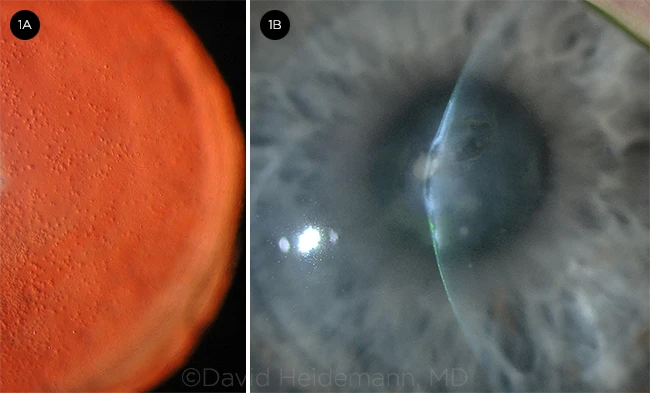

Fuchs dystrophy is a problem that occurs within one of the five layers of the cornea – the endothelium. The endothelium is the inner lining of the cornea, and it’s made up of a single layer of microscopic pump cells, which function to keep the cornea thin and clear.

In patients with Fuchs dystrophy, this endothelial layer becomes dysfunctional, and the pump cells start to die. As a result, the entire cornea may become swollen and hazy. Eventually, fluid-filled blisters may appear on the surface of the cornea, and one or both eyes may turn grey. This process is typically associated with a gradual reduction in vision and, over time, can become painful.

Low quality vision is the first sign, along with increased difficulty with tasks that require high visual performance, for example driving at night or reading under poor illumination. The world may appear less vibrant or less vivid. Color vision is often affected, with things appearing grey or “washed out,” particularly as the disease advances. Eventually, late-stage Fuchs dystrophy includes all of these symptoms, along with ocular pain, as blisters begin to form on the corneal surface.